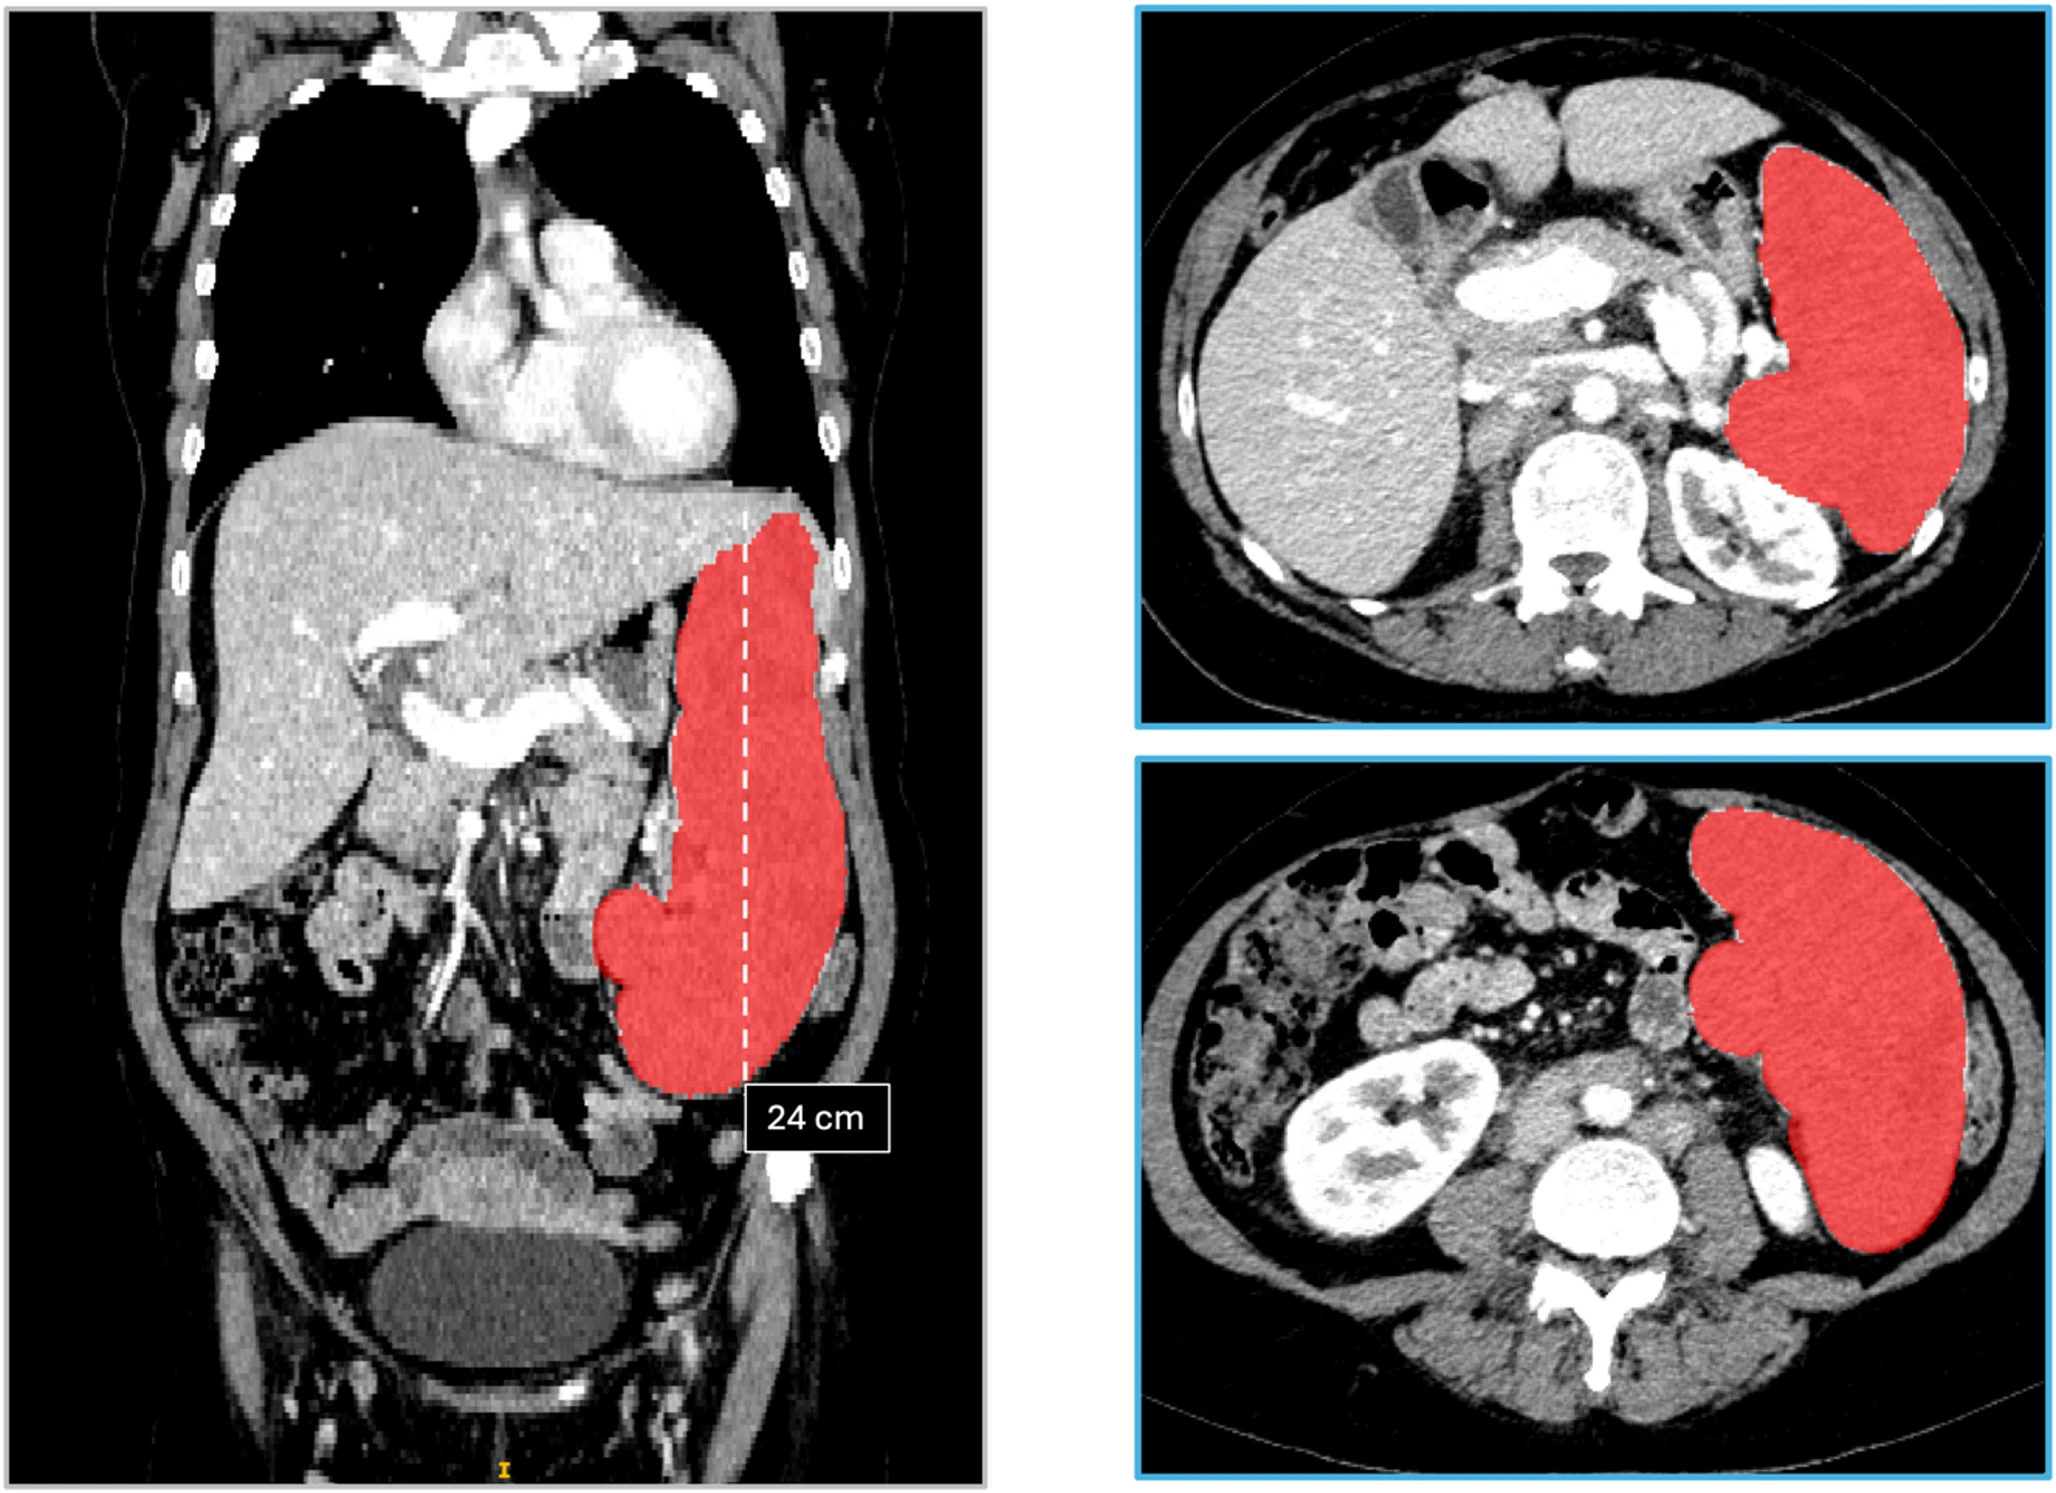

One project I contributed to involved segmentation and quantitative measurement workflows for spleen analysis on CT in patients with hematologic malignancies. This kind of work is a good example of the translational nature of the postdoc: computer vision methods were not being developed in isolation, but as part of a measurement pipeline tied to treatment response and clinical trial assessment.

CT segmentation figure showing spleen segmentation and measurement views.

An example of the segmentation-focused imaging work from my time at UW, where volumetric measurement and image analysis were central to the clinical question.

• Hasenstab KA, Lu J, Leong LT, Bossard E, Pylarinou-Sinclair E, Devi K, Cunha GM. Relationship between spleen volume and diameter for assessment of response to treatment on CT in patients with hematologic malignancies enrolled in clinical trials. Abdominal Radiology. 2025;50(12):5799-5809. DOI: 10.1007/s00261-025-05030-7